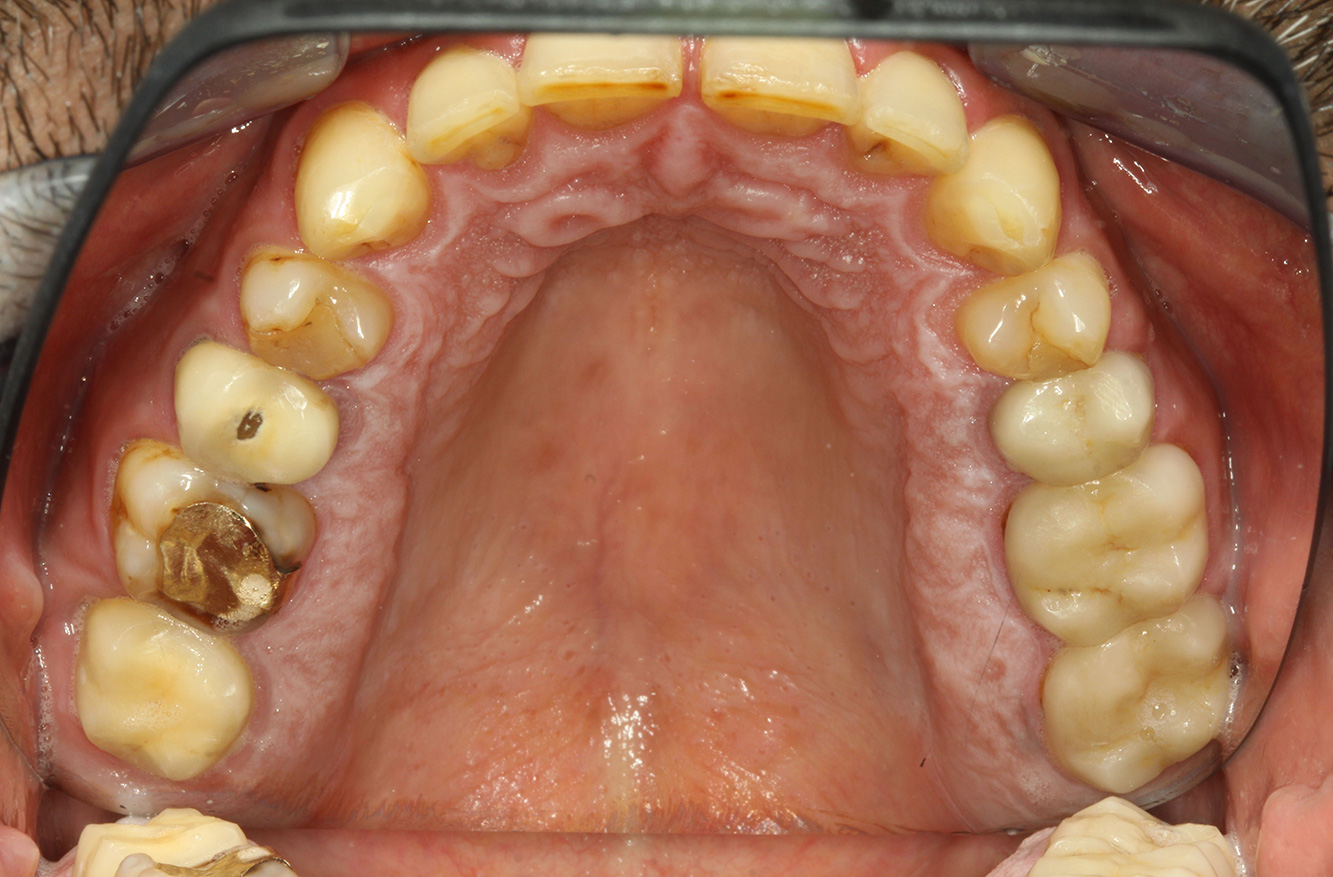

The endocarditis patient with active caries lesions*

The patient is 39 years old and has previously undergone aortic valve replacement due to valve failure and endocarditis. ASS 100 is taken regularly as an anticoagulant. In terms of lifestyle, the patient’s diet is classified as caries-promoting due to the regular consumption of sugary foods and the fact that six to seven meals are consumed daily. The patient’s oral health indicates a moderate risk of caries, with active lesions. The risk of periodontitis is low, but gingivitis is present. The following recommendations are made for prophylactic treatment.

The heart valve replacement and the history of endocarditis indicate an increased risk of complications. In order to reduce the risk of inflammation recurring, antibiotic prophylaxis is recommended (e.g. 2 g amoxicillin, 1 hour before the session). Despite the long-term blood-thinning medication, it is not expected that there will be an increased risk of bleeding in the prophylactic session.

Due to the active caries lesions and the associated risk of progression, a shortened recall interval of three to four months is recommended.